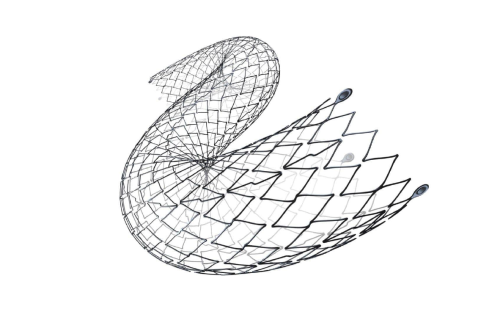

Na área de Cardiologia Intervencionista, fornecemos dispositivos de ponta, como stents, cateteres e balões, que são essenciais para a realização de angioplastias e outros procedimentos cardíacos minimamente invasivos. Nossos produtos são projetados para oferecer máxima eficiência e segurança, contribuindo para a rápida recuperação dos pacientes e a redução de complicações pós-operatórias.

Em Cirurgia Vascular, Endovascular e Radiologia Intervencionista oferecemos uma ampla gama de soluções, incluindo enxertos endovasculares, cateteres de trombectomia e dispositivos de embolização. Esses produtos são vitais para o tratamento de doenças vasculares complexas, como aneurismas e tromboses, proporcionando aos profissionais de saúde as ferramentas necessárias para intervenções precisas e eficazes.

Nossa atuação em Neurorradiologia Intervencionista inclui a oferta de microcateteres e stents especializados para o tratamento de aneurismas cerebrais e outras condições neurológicas críticas. Esses dispositivos são desenvolvidos com tecnologia de ponta para garantir a máxima segurança e eficácia durante os procedimentos, ajudando a preservar a integridade cerebral dos pacientes.